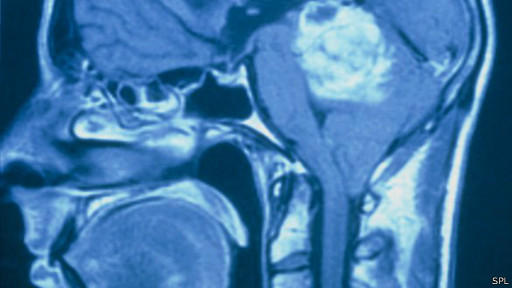

Предметом исследования были трудно поддающиеся лечению типы рака мозга - глиобастомы, которые имеют тенденцию распространяться в мозгу.

Раковая опухоль мозга обычно быстро распространяется